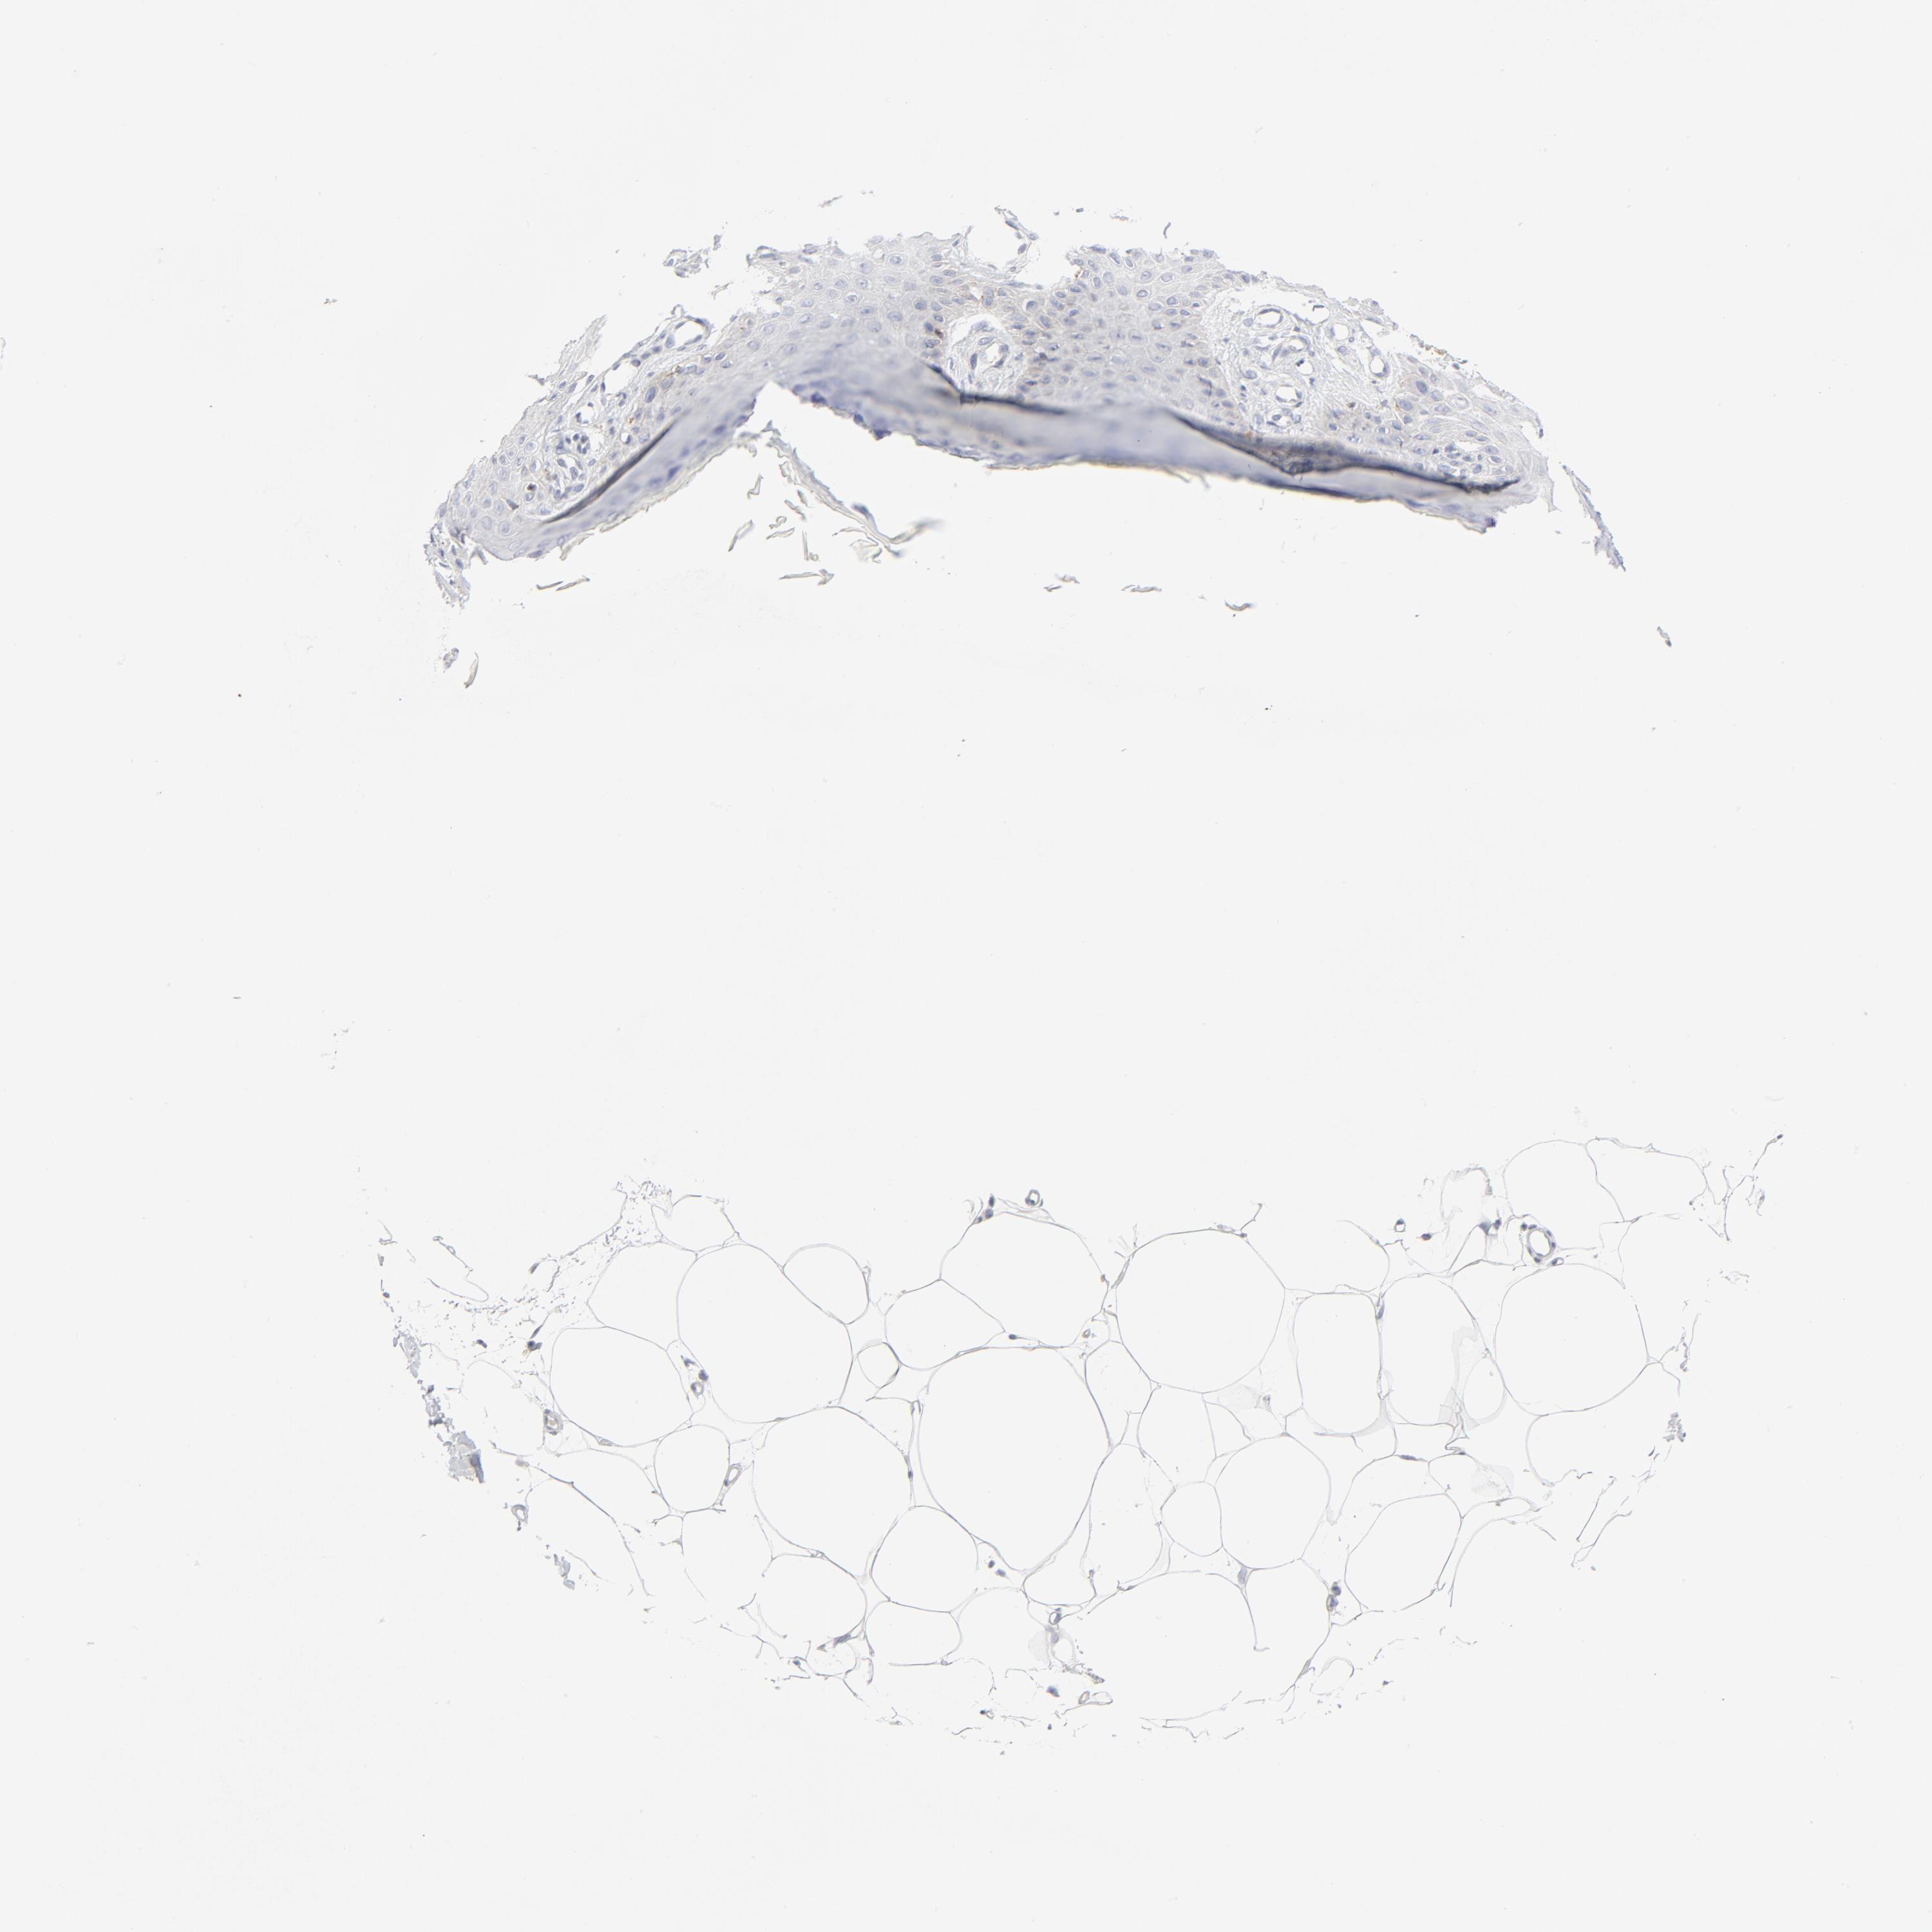

Basal cell and squamous cell cancer

SKIN CANCER - Protein expressioni

A mouse-over function shows sample information and annotation data. Click on an image to view it in a full screen mode. Samples can be filtered based on level of antibody staining by selecting one or several of the following categories: high, medium, low and not detected. The assay and annotation is described here.

Antibody stainingi

Antibody staining in the annotated cell types in the current human tissue is reported as not detected, low, medium, or high, based on conventional immunohistochemistry profiling in selected tissues. This score is based on the combination of the staining intensity and fraction of stained cells.

Each image is clickable and will lead to virtual microscopy that enables deeper exploration of all samples and also displays staining intensity scores, fraction scores and subcellular localization as well as patient and tissue information for each sample.

Antibody HPA029925

Antibody CAB004490

Basal cell carcinoma

Squamous cell carcinoma, NOS

Squamous cell carcinoma, metastatic, NOS